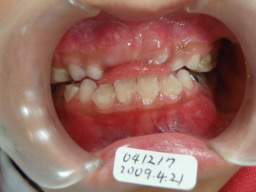

2008年04月23日(6才3ヶ月) 41番(右下切歯)がはえてきました。 反対咬合 |